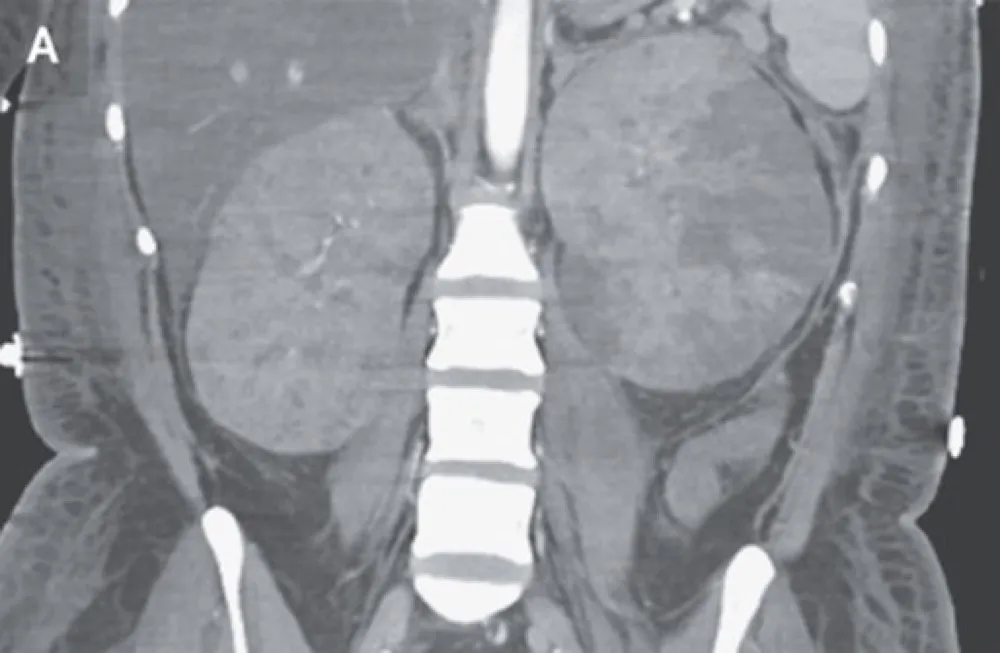

Particularidades da IRA e diálise no paciente cirrótico

Particularidades da IRA e diálise no paciente cirrótico